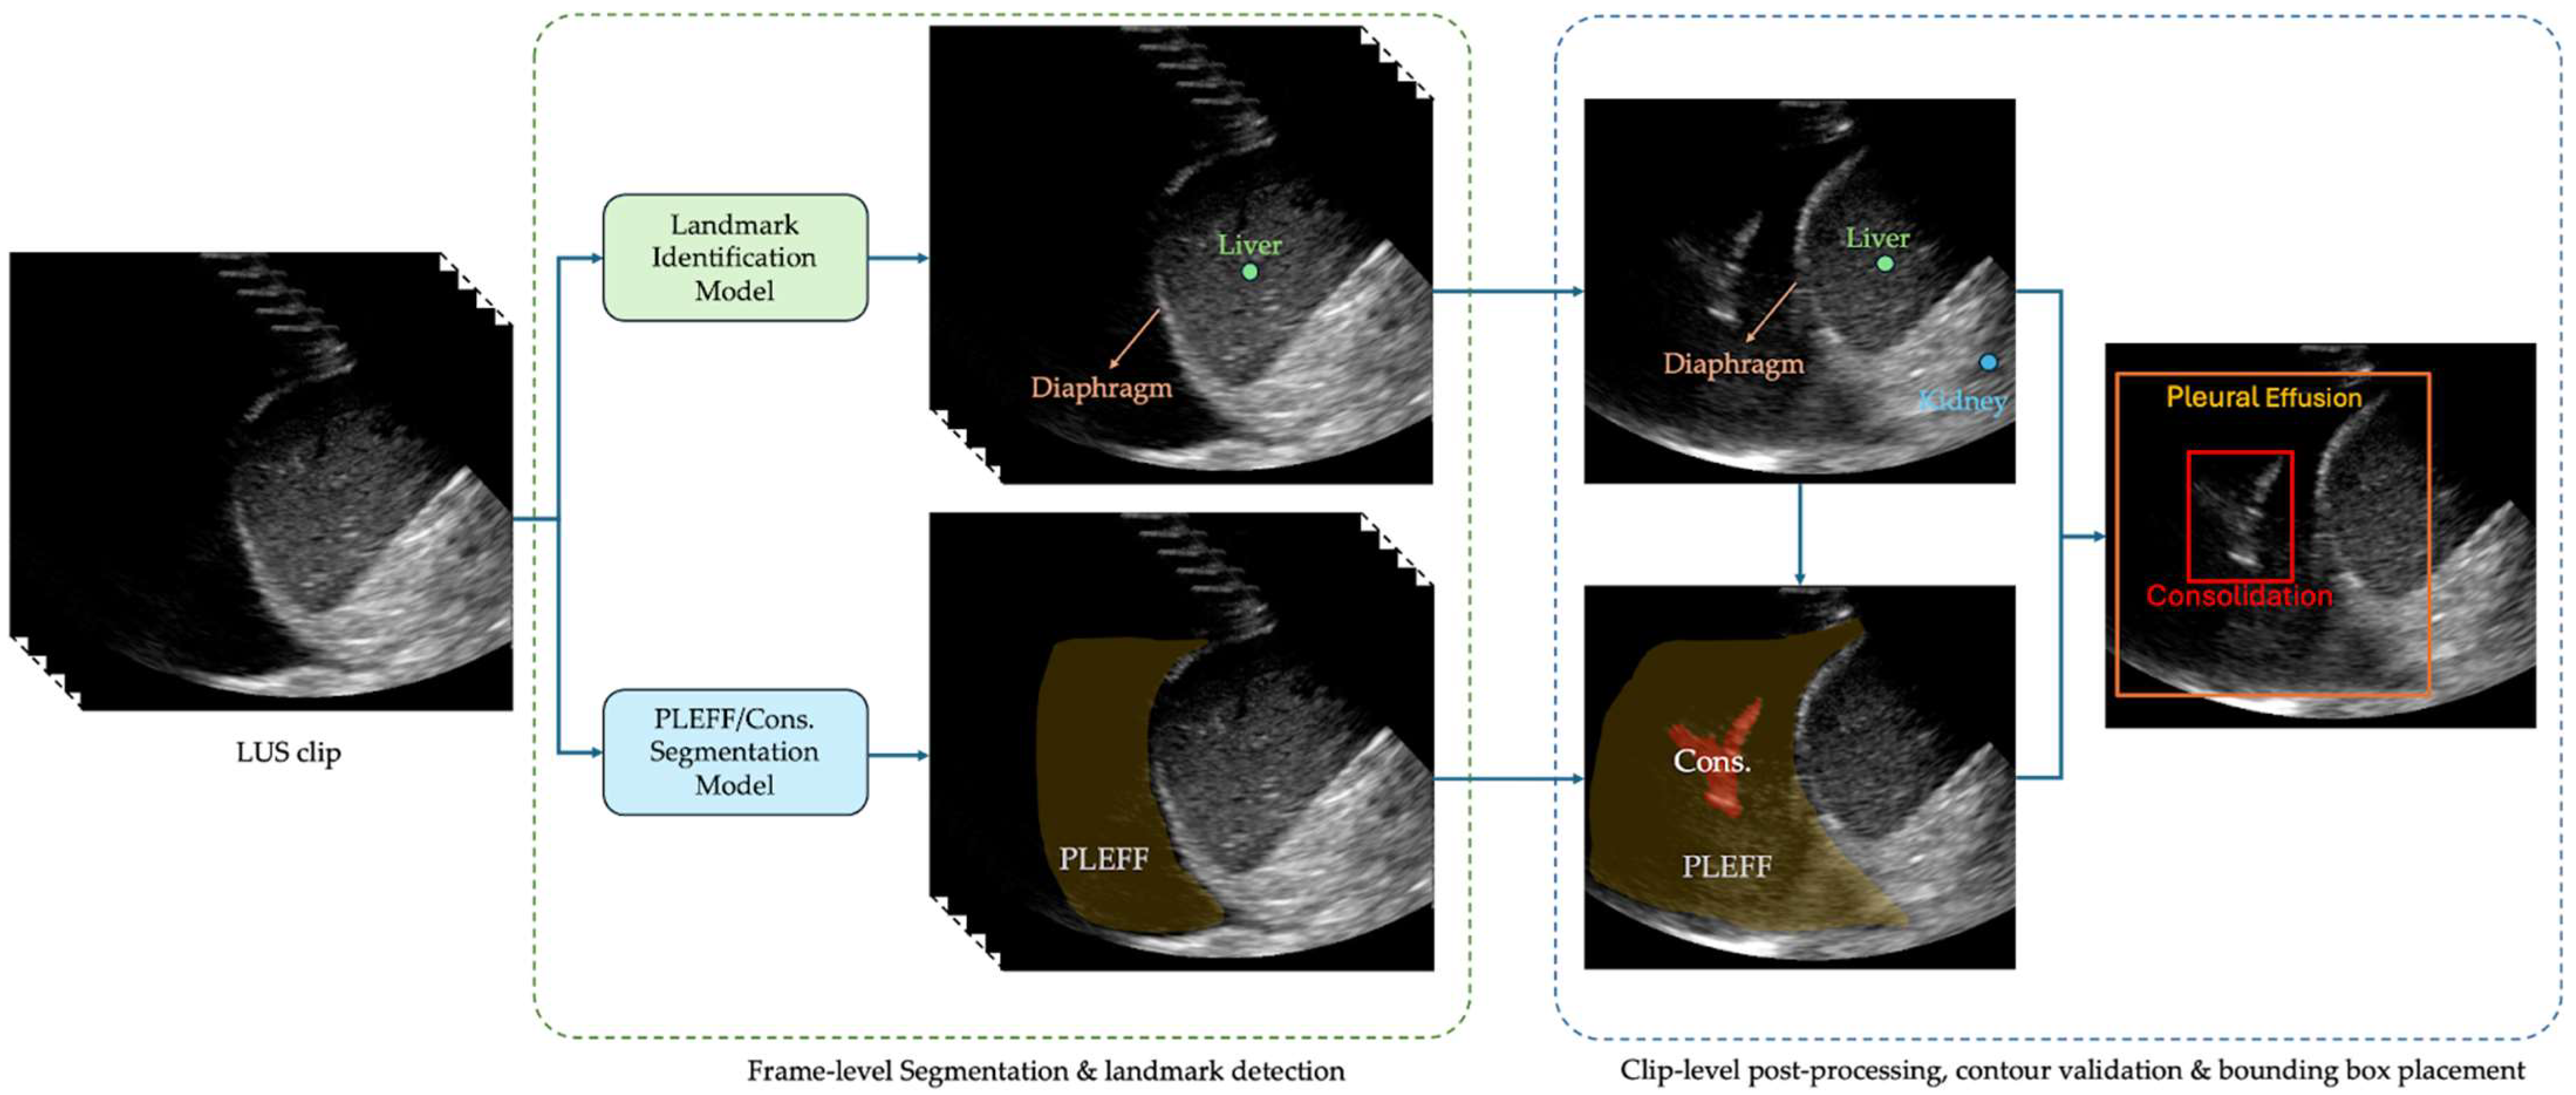

2.4. Exo Lung AI Software

The system uses a U-Net style architecture [28] for multi-class segmentation to identify pleural effusion and consolidation/atelectasis across individual frames. In parallel, a landmark detection model identifies key anatomical structures of the lung, such as the diaphragm, liver/spleen, and kidney. Per-frame outputs are then stored and processed collectively at the clip level. During this post-processing phase, a contour validation algorithm assesses the validity of the predicted effusion and consolidation masks based on their relative position to the anatomical structures. A clip is classified as positive for a condition if at least one frame contains a validated contour for the corresponding pathology. The algorithm selects the frame with the largest valid pathological contour for the region of interest placement. The box of the region of interest is then overlaid on the corresponding image and shown to readers during interpretation. An example of these bounding boxes is shown in Figure 1.

Figure 1. An example of the produced bounding boxes for pleural effusion and consolidation/atelectasis.